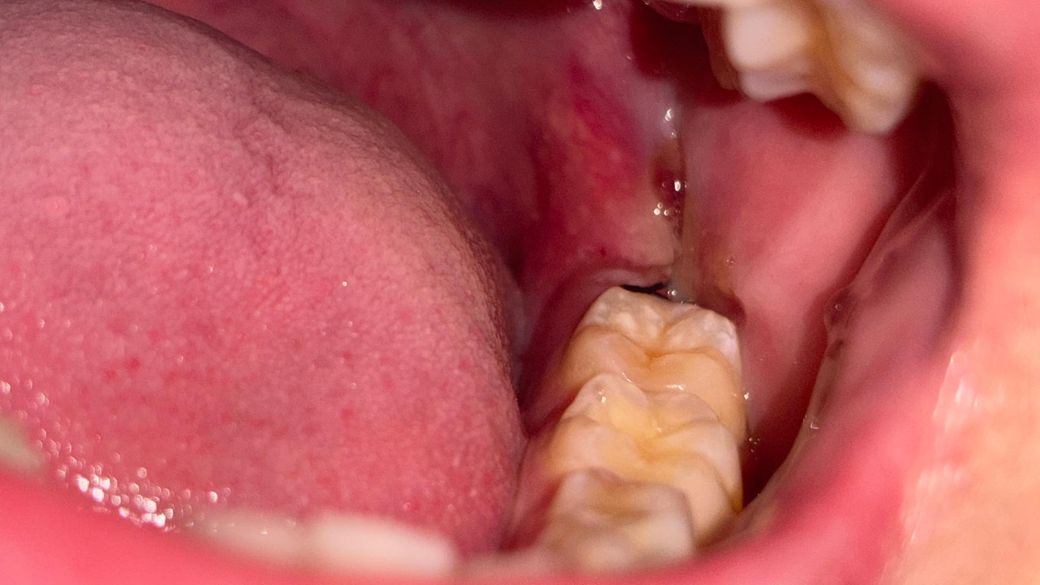

사랑니 발치 후 상태입니다. 사랑니 위, 아래 한 개씩 (아래는 매복) 뽑은 상황입니다.

사랑니 발치 후 하루 정도 뒤 상태인데 괜찮은 건가요??

남들은 피덩어리? 가 생긴다는데 저처럼 생긴건 인터넷에 쳐도 잘 안나오더라고요...

• 1번 째 사진

사진찍은 부위는 발치 한 곳 뒷부분이고요. 그 앞 어금니에 가려 잘 안보이는거지 상태는 괜찮아보입니다. 봉합 상태도 좋고요

사진상으로는 양호한 치유양상을 보이는 것으로 보입니다. 크게 걱정하실 것 없어보이며 혈병은 발치와 내로 형성되므로 환자분들이 보는것은 어려울 수 있습니다.